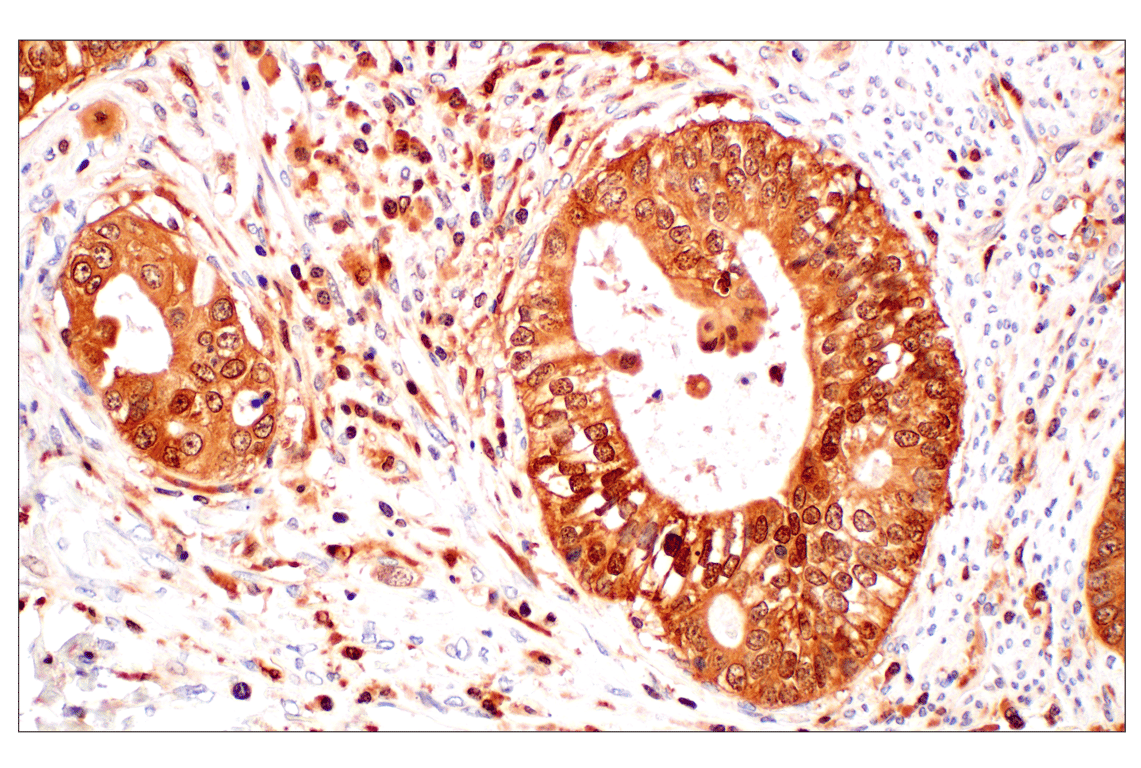

Immunohistochemical analysis of paraffin-embedded human endometrioid adenocarcinoma using GPX4 (E5Y8K) Rabbit mAb.

Immunohistochemistry Image 2: GPX4 (E5Y8K) Rabbit Monoclonal Antibody